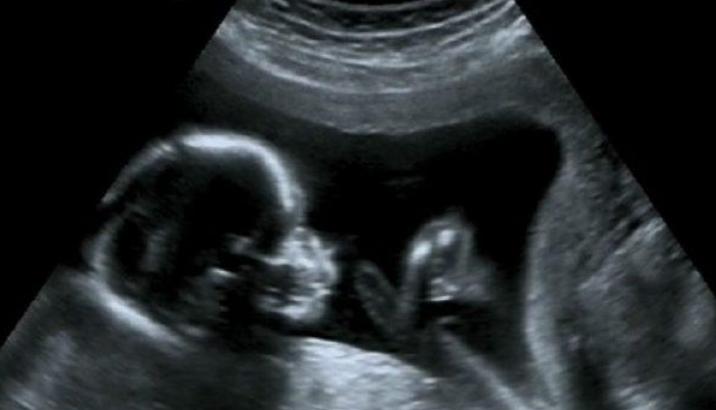

小静是一个司机,在怀孕期间也依旧出车,为了给孩更好的生活,和老公都没有停下脚步一直在打拼,而这天要去做B超了,是四维的,因为宝宝比较调皮他溜达了好久才拍到宝宝的全身。

结果看到宝宝动态的时候大家都傻眼了,因为这个小宝宝正在继承妈妈的事业,那小手小脚明显就是在打转向踩油门的姿势,不得不说还真是标准,网友看到之后都表示:“这也太神奇了,未来是个神车手啊!”。